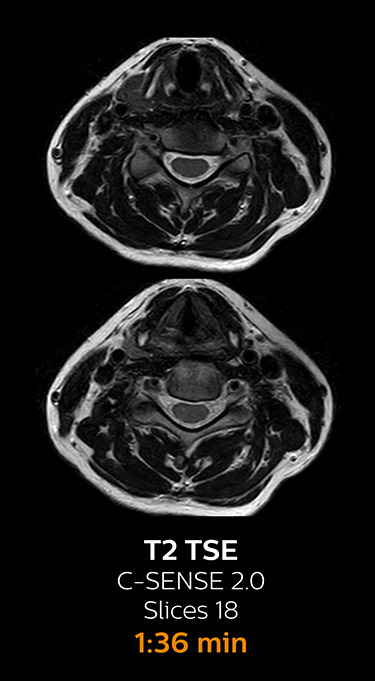

Fast MRI of cervical spine

With Compressed SENSE, the scan time for the routine cervical spine examination at KNC was reduced from 13:11 to 9:52 minutes, which corresponds to 25% reduction.

MRI examination of cervical spine with Compressed SENSE

MRI examination of the cervical spine with Compressed SENSE

Ingenia 3.0T CX

Scan time 9:52 min. (was 13:11 min. without Compressed SENSE)